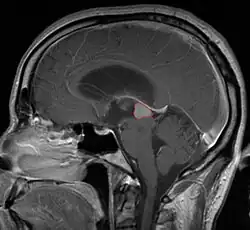

Radiation Oncology/CNS/Pineal

Pineal Gland Tumors

• Determined by the spatial anatomy and direction of growth

• Obstruction of aquaduct: hydrocephalus presenting as headaches, nausea, vomiting

• Compromise of superior colliculus: vertical gaze palsy, pupillary and oculomotor nerve paresis (Parinaud syndrome)

• Work-up includes MRI, CSF, serum markers for bHCG and AFP